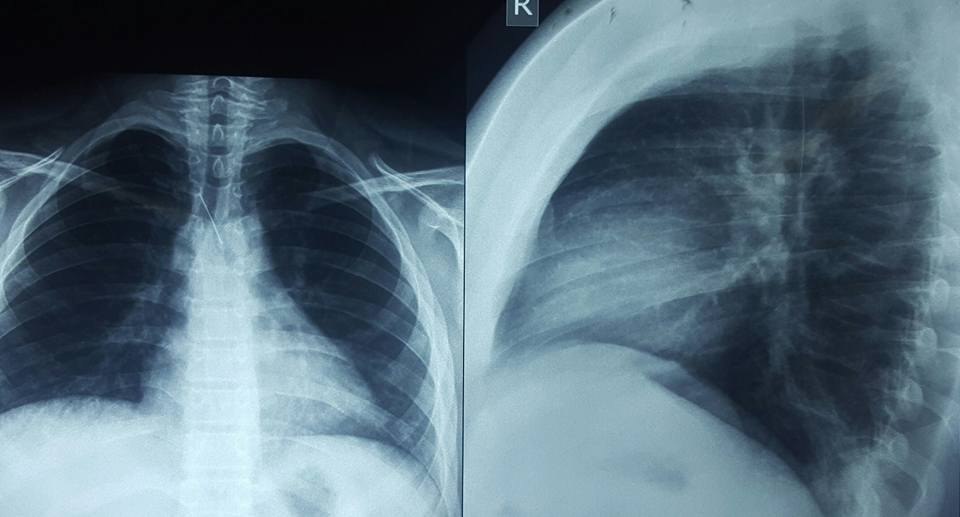

وقال رئيس الفريق الاستشاري في جراحة الصدر والقلب والأوعية الدموية بكلية طب الأنبار، الطبيب محمد طفش، اليوم الجمعة (12 مايو/ايار 2017)، إن "عملية ناظورية اجريت لشاب يبلغ من العمر 16 عاما في مستشفى الفلوجة التعليمي وبمشاركة كادر طبي متخصص، تم خلالها استخراج دبوس من القصبة الهوائية للشاب الفلوجي من خلال عملية استئصال ناظورية دون تدخل جراحي وتكللت العملية بالنجاح التام".

وذكر طفش انه "بعد التشخيص الدقيق لحالة المريض وتحديد مكان استقرار الدبوس من قبل الفريق الطبي وبإشراف طبيب التخدير نزار حامد العبيدي، تم اجراء العملية بنجاح وقد استغرقت ساعة واحدة فقط بعملية ناظورية دون تدخل جراحي"، مضيفا "ان المريض يتماثل للشفاء بعد خروجه من صالة العمليات".